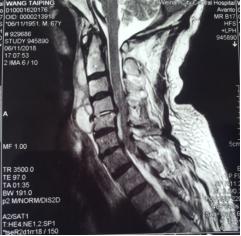

来市中心医院后,患者四肢肌力上肢1-2级,下肢1级。双下肢腱反射未引出。自胸骨柄以远躯干部位感觉减退。入院后给以各项常规检查,血常规显示白细胞计数12.54×109/L,中性粒细胞绝对值10.85×109/L,,中性粒细胞百分比86.5%,血沉22mm/h,超敏C反应蛋白69.4mg/L。空腹血糖13.88mmol/L。颈椎核磁检查显示颈4/5椎间隙狭小,颈4.5.6椎体T1像低密度,椎体前缘出现炎性浓集。入院初步诊断:颈椎体感染,合并椎间隙脓肿形成,四肢不软瘫,糖尿病II型。在治疗早期即给以广谱抗生素头孢哌酮舒巴坦钠静滴.3.0g,q8h;并口服莫西沙星片,0.4g,qd,使用阿卡波糖控制血糖。再次完善相关检查。全身放射性同位素骨扫描未见肿瘤表象。结核TB淋巴细胞斑点试验阴性,布氏杆菌滴度测定阴性。经治疗,患者体温平稳,血沉,超敏C反应蛋白水平下降明显。后期再次复查颈椎核磁,发现颈椎椎体4.5前缘形成更大的积液表现,椎管内也有形成。随后在B超定位下行颈前肿物穿刺抽吸术,抽出含血浑浊液2ml,分泌物抗酸染色阴性,常规染色图片发现多量的阳性球菌,细菌培养3未见细菌生长。